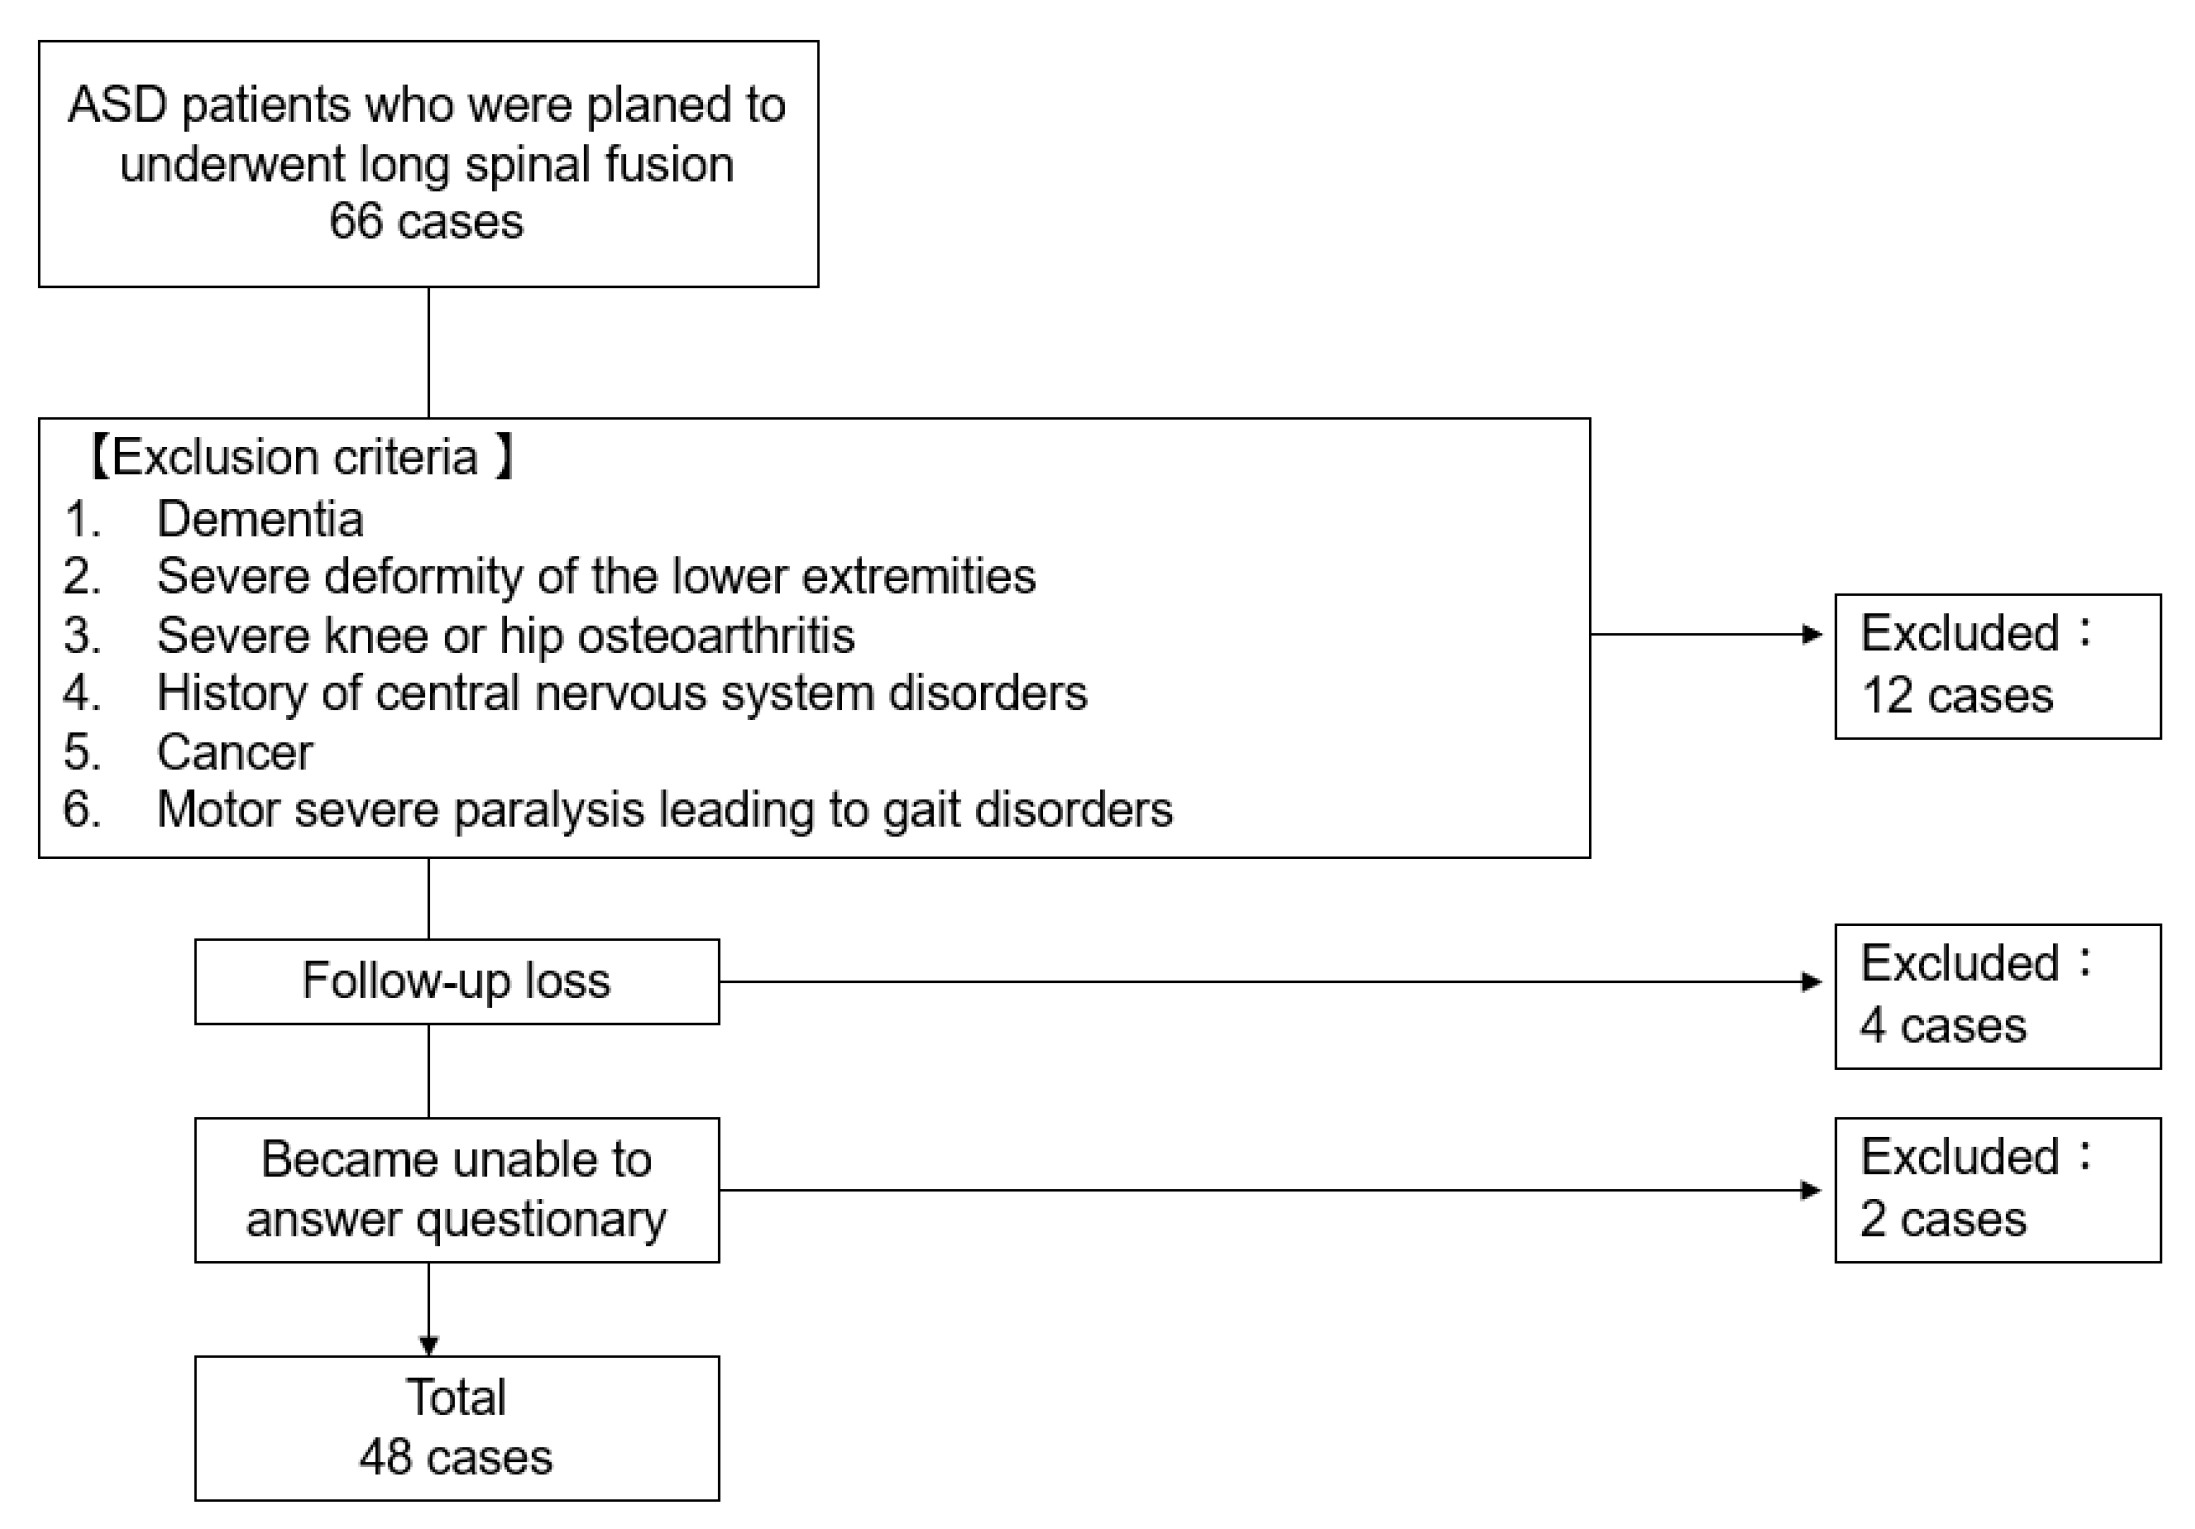

2. Materials and Methods

2.1. Patient Demographics